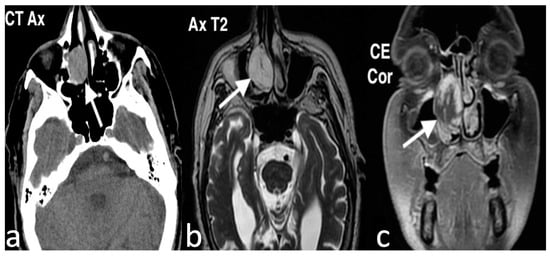

3.2.4. Inverted Papilloma

3.2.5. Osteoma

3.2.6. Hemangiopericytoma